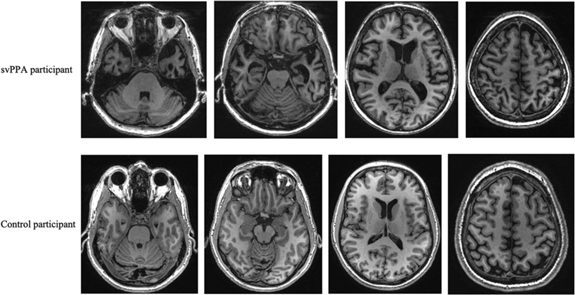

Volumetric data showed that both groups had indistinguishable total intracranial capacity and total brain volumes. However, our group of svPPA patients had smaller subcortical and left hemispheric cortical GM volumes. When looking at specific ROIs, volumes were consistently lower in svPPA patients than in healthy controls, reaching significance in 22 of the 33 studied regions, after FDR correction. The most significant differences were noted in the left amygdala, entorhinal, fusiform, inferior temporal, middle temporal and superior temporal gyri, as well as in the temporal poles and right fusiform GM (see Table 3 and Figure 2).

Figure 2: GM images: examples of atrophy in a svPPA patient compared with a cognitively healthy control. svPPA, semantic variant of primary progressive aphasia.

Our first aim was to characterise cerebral WM lesions in our cohort of svPPA patients, compared with cognitively healthy, age-matched control subjects. Using a tract-based whole-brain approach, we found FA differences between our two groups, including statistically lower FA in the right hippocampus and uncinate fasciculus tract regions, as well as the left external capsule and superior longitudinal fasciculus tracts. Our second aim was to characterise cerebral GM lesions in these same patients. Using volumetric tools, we found significant atrophy differences between patients and controls. Notably, larger GM atrophy in svPPA patients was found in the left amygdala, in the left entorhinal, fusiform, inferior temporal, middle temporal and superior temporal gyri, left temporal pole and right fusiform gyrus.

Our GM results showed a lateralisation of atrophy related to svPPA, as it was more severe in the left hemisphere. We also found significant atrophy in the temporal lobes. These results are in line with those previously described in literature.Reference Wilson, Joubert and Ferré40 This is also in accordance with fundamental neuroimaging studies on the cerebral regions associated with language,Reference Wilson, Joubert and Ferré40 which have shown that the left anterior temporal lobe is part of the semantic brain network, whereas other functions like syntax would be processed more in the posterior temporal or frontal lobes.